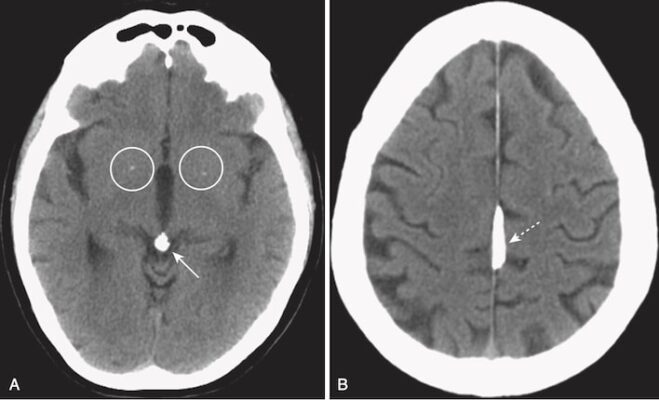

- Phù não được chia thành hai loại chính: do mạch máu và do nhiễm độc tế bào (Hình 14).

- Phù não do mạch máu (Vasogenic edema) thể hiện sự tích tụ dịch ngoại bào và là loại có liên quan đến bệnh ác tính và nhiễm trùng. Nguyên nhân là do bất thường tính thấm của hàng rào máu não. Phù não này chủ yếu ảnh hưởng đến chất trắng (xem Hình 14, A).

- Phù não do nhiễm độc tế bào (Cytotoxic edema) biểu hiện phù tế bào và có liên quan đến thiếu máu não cục bộ. Phù não này là do chết tế bào và ảnh hưởng đến cả chất xám và chất trắng (xem Hình 14, B).

- Nhận biết phù não:

- Mất sự phân biệt bình thường giữa chất xám và chất trắng trong phù do nhiễm độc tế bào.

- Có thể có hiện tượng xoá mờ (đè nén hoặc bít tắc) của các nếp gấp vỏ não (sulci) bình thường.

- Các não thất có thể bị đè ép (Hình 15).